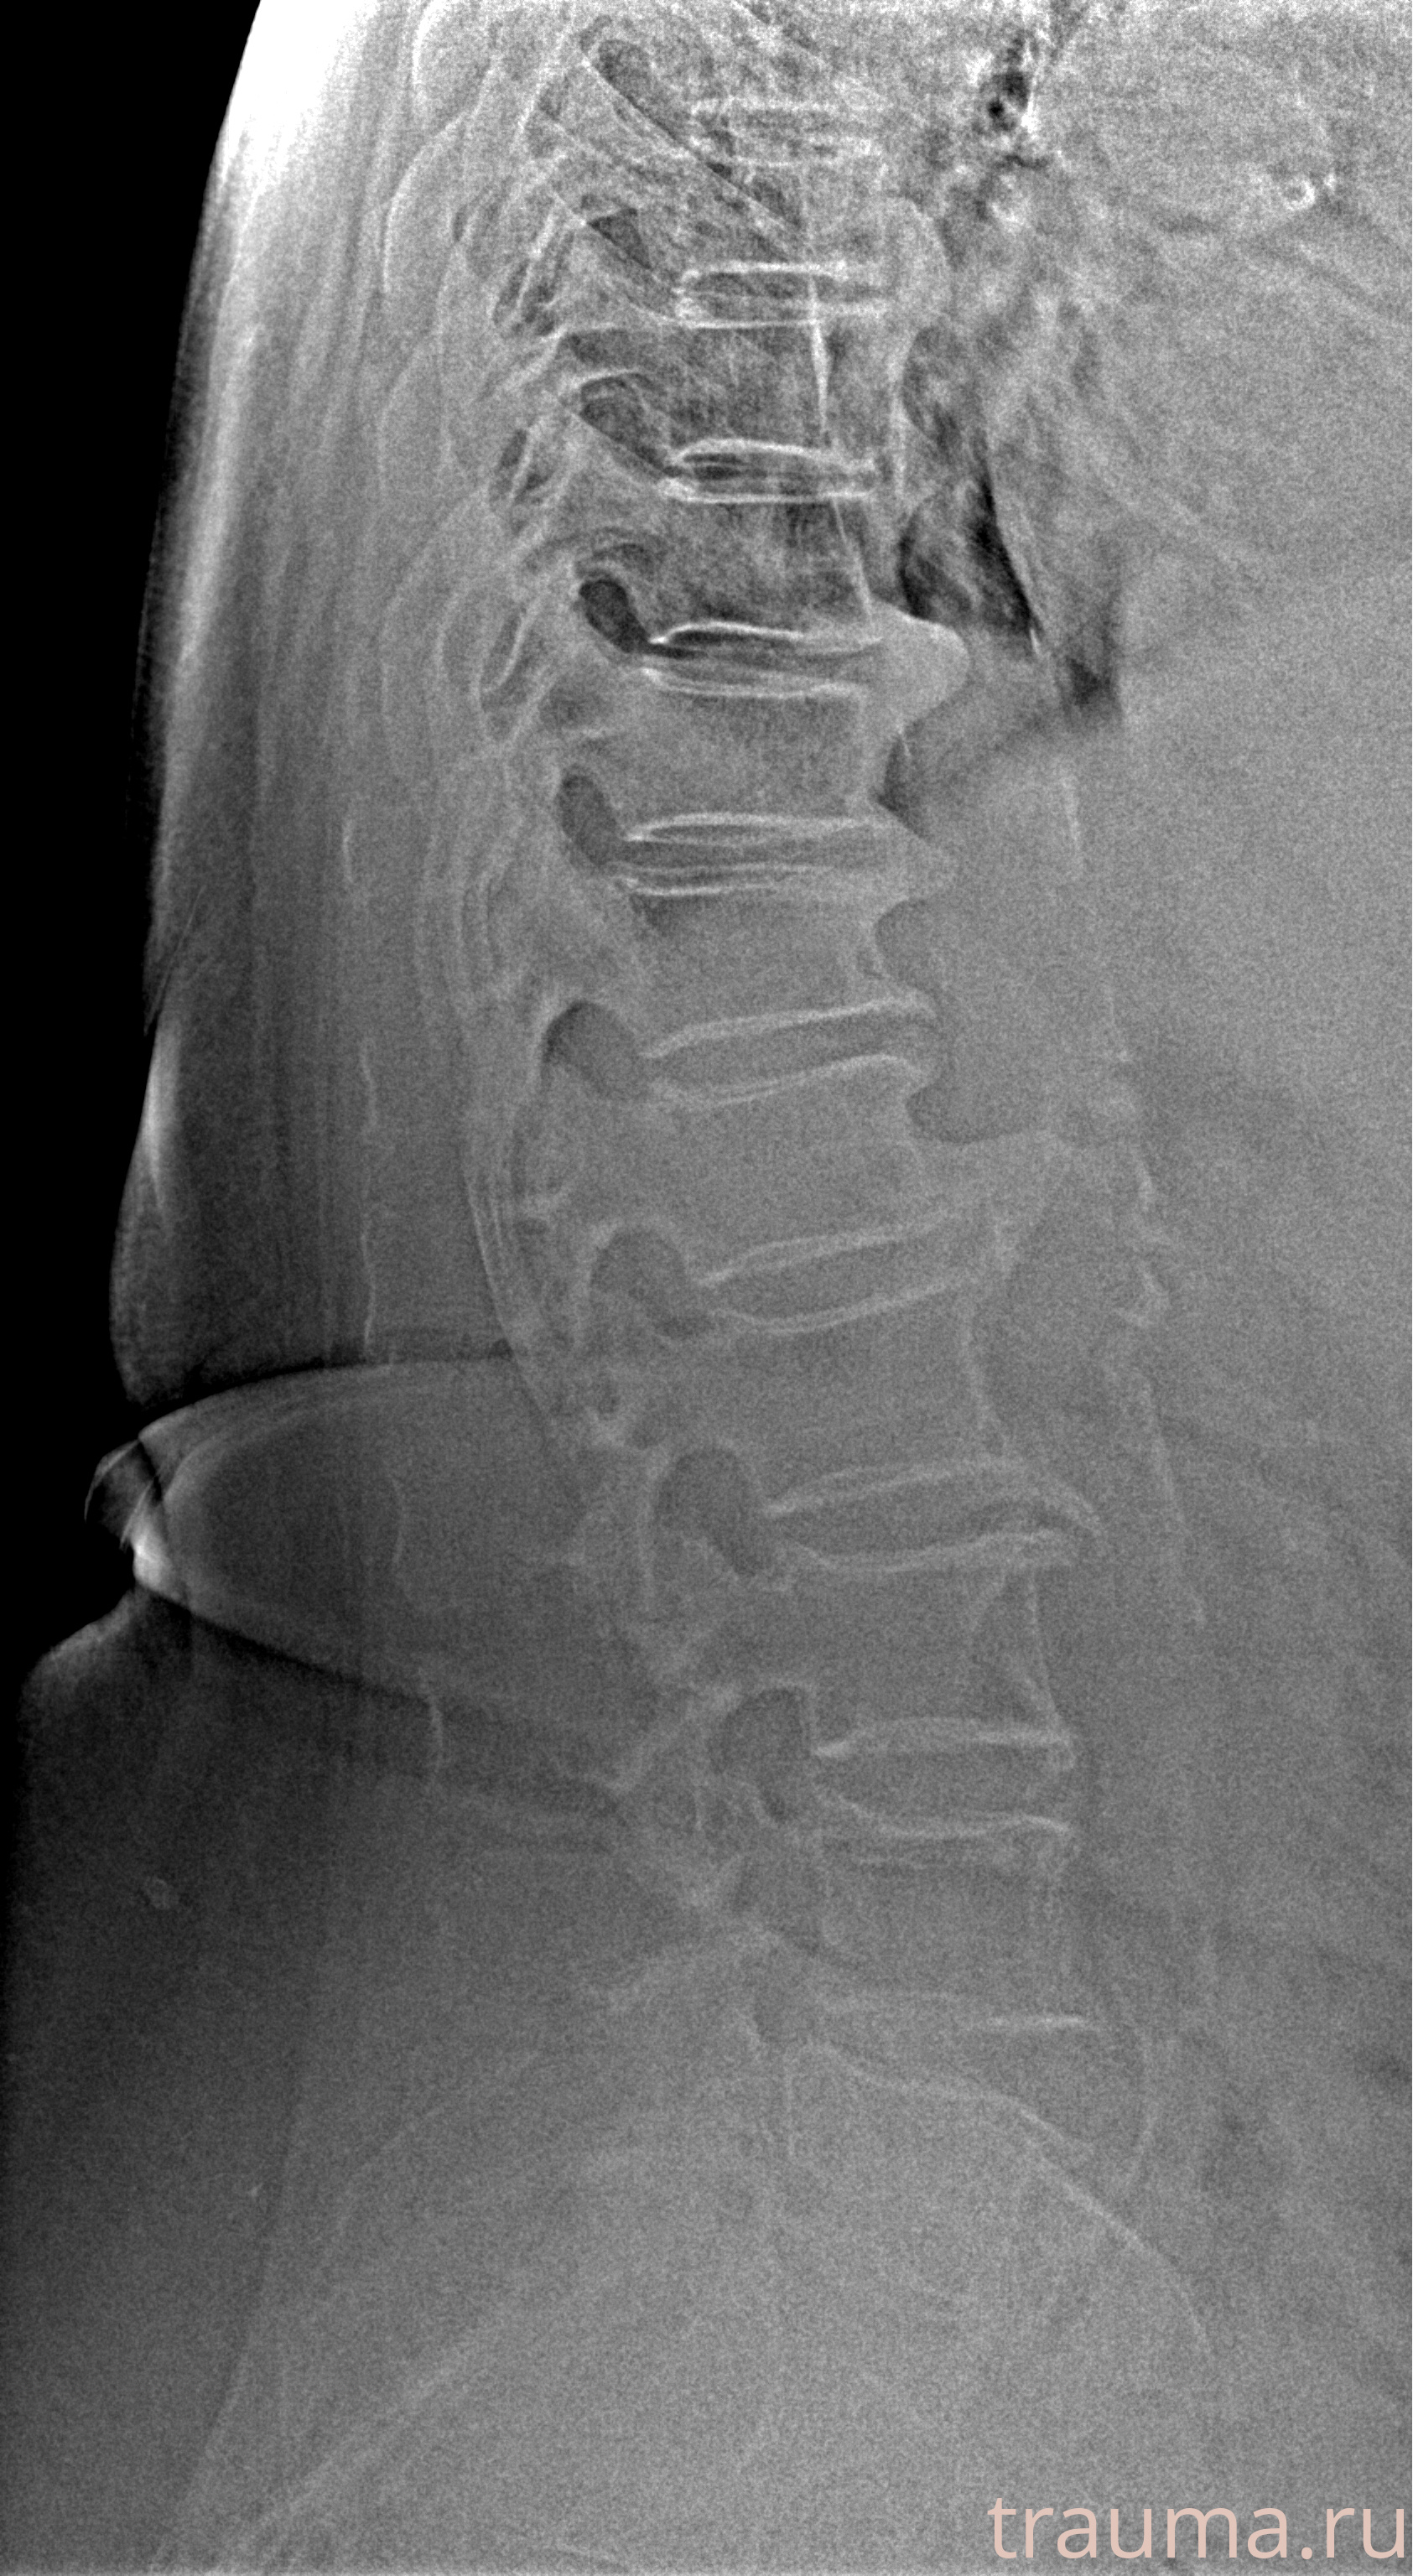

Рентген на дому: по вашему адресу приезжает врач-рентгенолог, травматолог-ортопед с мобильным рентгеновским аппаратом, проводит диагностику травмы или заболевания, делает необходимые рентгенограммы, дает рекомендации по дальнейшему лечению. Получить качественные снимки в домашних условиях возможно благодаря уникальной методике, разработанной МосРентген Центром для института  Склифосовского